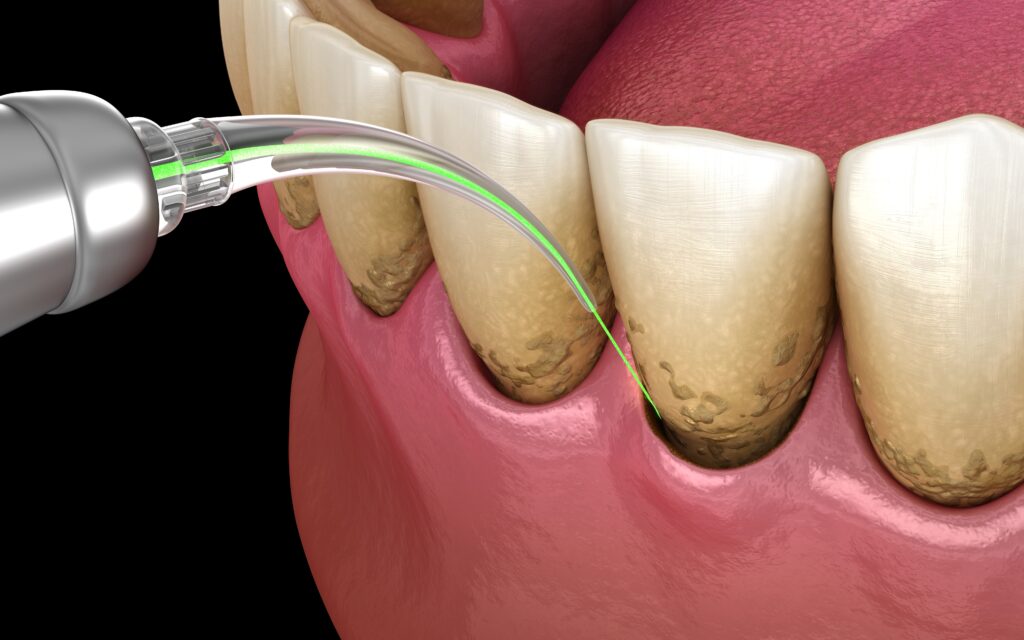

Terapia fotodynamiczna

Dopełnieniem terapii FMD jest terapia fotodynamiczna, mająca na celu pełną dezynfekcję jamy ustnej z agresywnych bakterii, grzybów, wirusów i pierwotniaków

- Do kieszonek dziąsłowych aplikowany jest fotouczulacz, naświetlany światłem lasera FotoSan rozbija wszelkie drobnoustroje chorobotwórcze

- Po terapii fotodynamicznej pacjent otrzymuje probiotyk w tabletkach do ssania na 30 dni, aby wprowadzić “dobre” bakterie do jamy ustnej